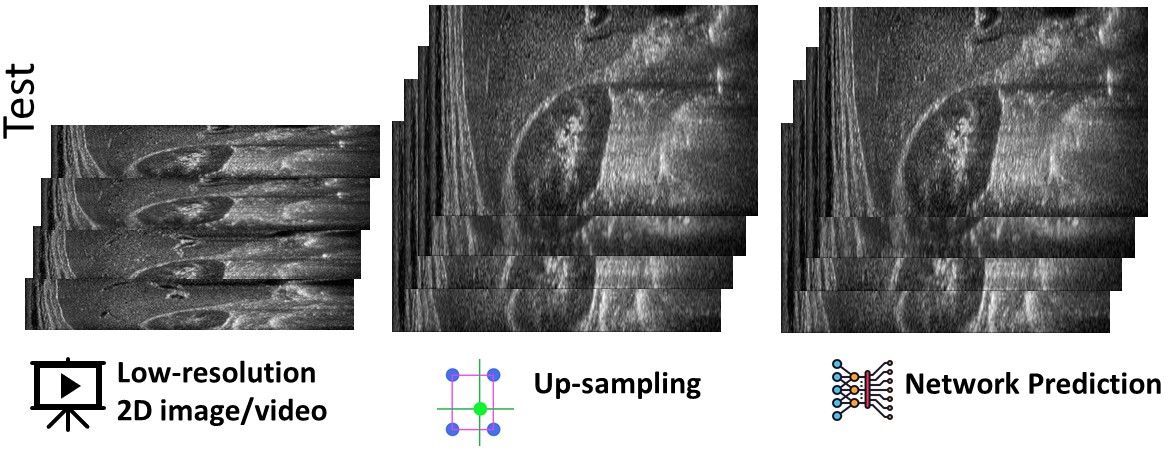

4.3 Proposed super-resolution of US videos

Applying our approach to US videos with a low spatial resolution and a high frequency (e.g., for the cardiac district), we can generate high-frequency 2D US video with an increased spatial resolution of each frame, thus overcoming the main limits of current US probes, whose spatial resolution decreases as the acquisition frequency increases. The relationship between image resolution and video frequency is given by , where is the speed of sound. The acquisition of low-resolution US images allows the physician to increase the acquisition frequency. The probe acquires a reduced number of lines: we refer to 0.5X and 0.25X low-resolution images, as and resolution, respectively. We refer the reader to the uploaded video for the experimental tests on the spatial super-resolution of 2D US videos (see URL below). In the video, the input signal is a 2D US video at full resolution with lines, depth, and frames. We down-sample each image at or , and apply our framework for the spatial super-resolution, to reconstruct the full-resolution 2D video. Video URL: https://www.dropbox.com/s/p42pzxxvgf9gacl/SuperResolution-US.mp4?dl=0.